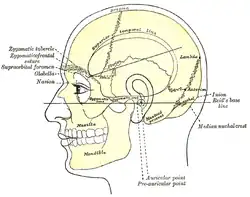

| Side view of head, showing surface relations of bones. (Mastoid process labeled near center.) | |